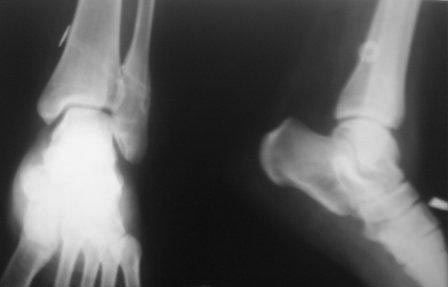

Обратилась К.19 лет. Со слов матери 10-12 лет назад получила перелом лодыжек, лечилась консервативно, ч-з год повторно получила травму г/стопного сустава, лечилась консервативно.

С тех пор беспокоят периодические боли, отеки, слегка прихрамивает. Неоднократно лечились амб и стац, в разных отделениях. 1,5 год назад в одной б-це произведена операция фиксация дистального м/б синдесмоза болт -стяжкой , и через год удалена м/конструкция и вся клиника повторилось. Девочка упитанная, . Мне кажется у б-ной был чрезсиндесмозный оскольчатый перелом м/б кости с разрывом переднего отд.синдесмоза, (44В1.3). неправильное сращение и укорочение м/б кости, или даже с поворотом. , за счет этого хр.неустойчивость дистального межберцового синдесмоза. И к тому болт –стяжка проведена неправильно,с нарушением техники и результат- 0.

Предварительно думаем: косая надсиндесмозная остеотомия м/б кости, удлинение и адаптация мед.суставной поверхности наружной лодыжки, фиксация 1/3 трубчатой пластиной, ревизия дистального синдесмоза, возможно пластика синдесмоза(пока незнаю чем) , и две позиционного винта, или болт –стяжка. Еще будем глубже заниматься, КТ не работает, МРТ есть.